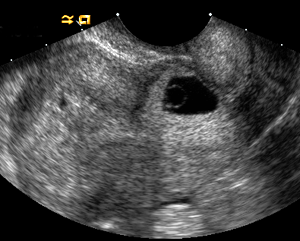

Dandy Walker Malformation.